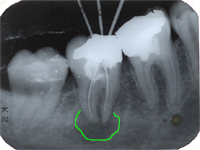

Im Röntgenbild von Abb. 3 ist ein gut erbsengrosses Granulom (Pfeil) an der Wurzelspitze eines toten, devitalen Zahnes feststellbar. Die Patientin wünschte die Erhaltung des Zahnes, zumal auch der vordere Nachbarzahn marktot und beherdet war. Abb. 4 zeigt das Röntgenbild nach der Wurzelfüllung.